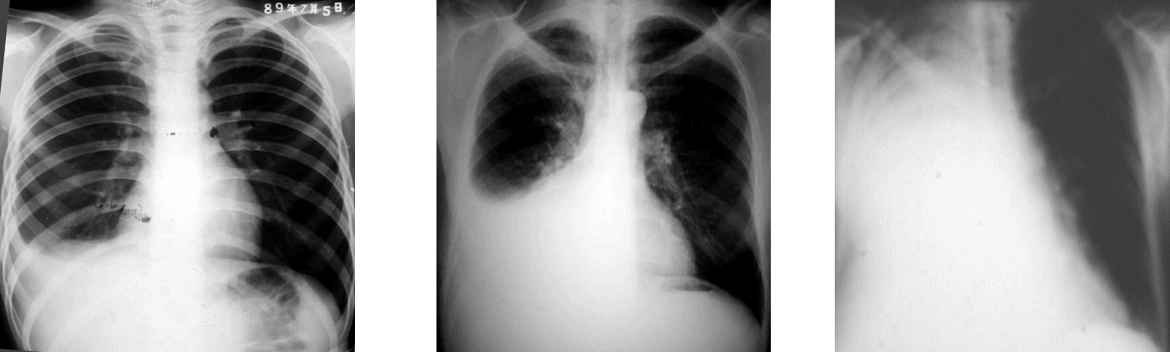

(5)气胸:继续使用导课的病例,说明气胸后出现病情变化,结合X线改变,讨论其体征产生机制,再次把以病人为中心的理念告知学生,把思政融入课堂。准备一张单纯气胸X线改变,一张COPD合并气胸CT改变(导课病人),与学生讨论其不同的体征及产生原因。(8min)